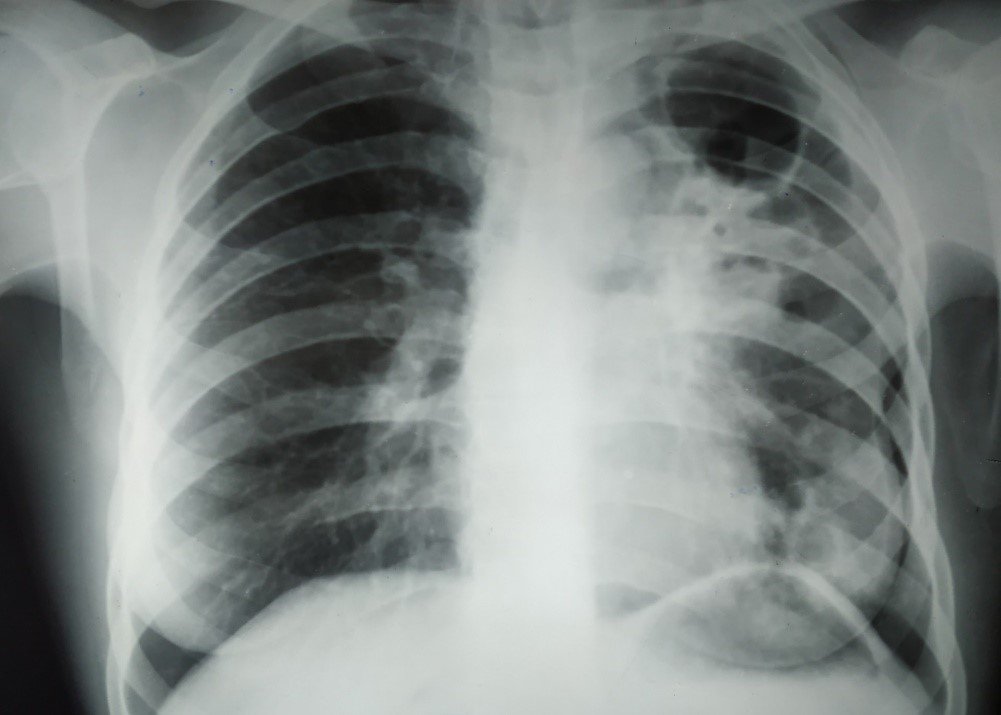

Що треба знати про туберкульоз

У березні розпочався Місячник обізнаності про туберкульоз. Запитали в генеральної директорки Харківського обласного центру контролю та профілактики хвороб Любові Махоти про те, що треба знати кожному дорослому про убезпечення себе й дитини. Чи досить вакцин БЦЖ, проти грипу, коронавірусу й гепатитів? Прості алгоритми, що можуть урятувати життя.